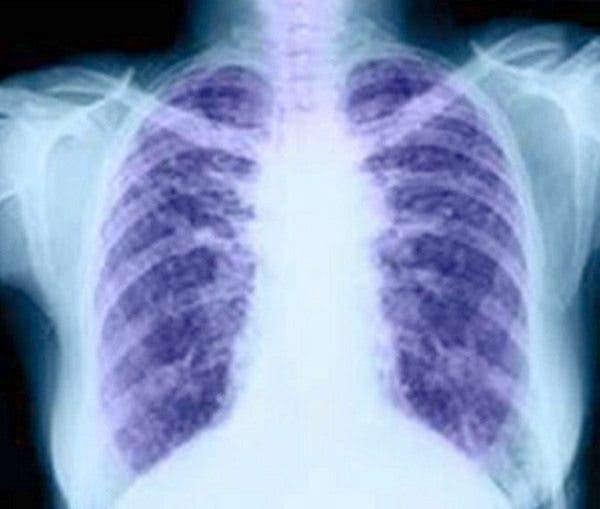

El tromboembolismo pulmonar, también conocido como embolia pulmonar, es una de las complicaciones más graves derivadas de la formación de trombos en el sistema circulatorio.

La oclusión, por tanto, afecta sobre todo a los pulmones y al corazón, de modo que una zona de los pulmones recibe sangre pobre en oxígeno, y como no se puede oxigenar adecuadamente, perjudica la llegada de dicho oxígeno al resto de órganos.

El diagnóstico suele apoyarse en pruebas como el análisis del D-dímero, un marcador de coagulación que se eleva cuando existe formación de trombos, y en estudios de imagen como el TAC o la ecografía de miembros inferiores.

Estas herramientas permiten confirmar la presencia del coágulo y determinar su localización exacta.